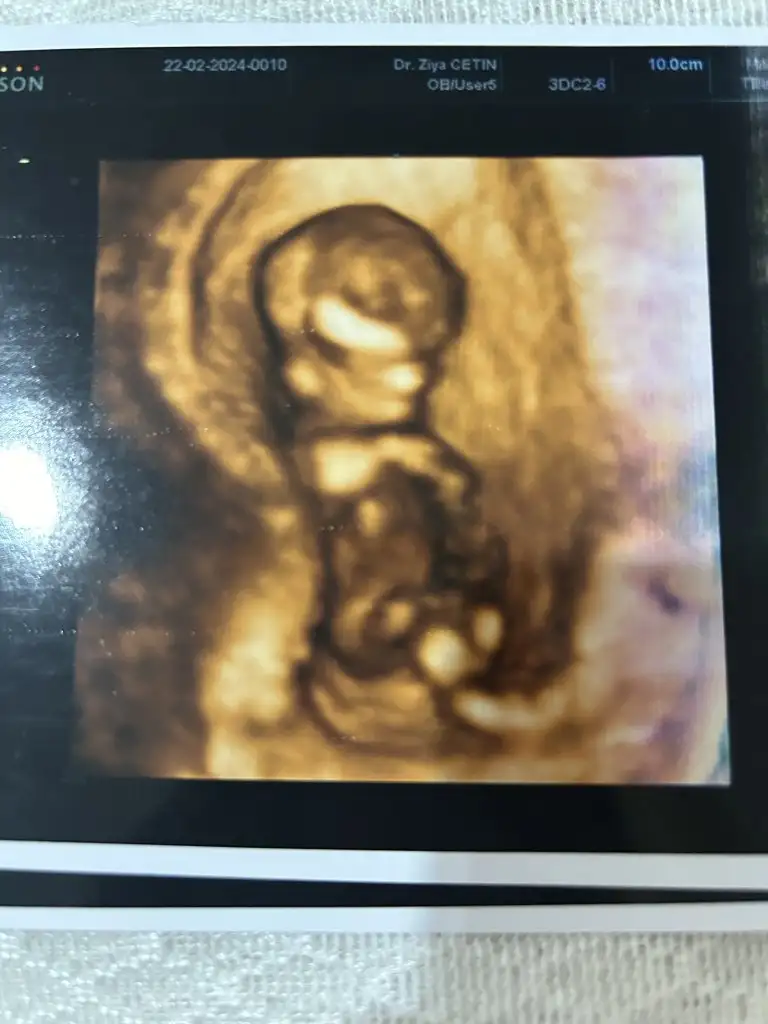

Bu da benimki 14+4 olduk bir bakın kızlar sizce ne doktor belli değil dedi henüz. Bir başka doktor da erkek gibi duruyor dedi bilemedik valaKızlar bebişlerinizin ultrason resimlerini ve cinsiyetini kaçıncı haftada olduklarını yazında kendi ultrason resimlerimizle kıyaslayıp fikirde bulunalım. Nub teorisi, kafa şekli, kemik yapısından cinsiyet teorileri tutuyor mu bakalım bir